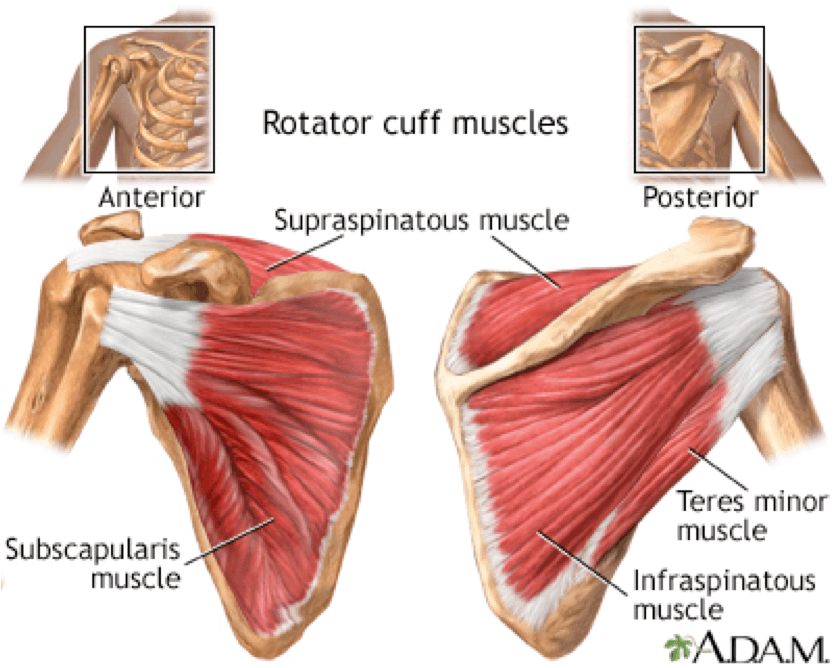

Фотографии мышц ротаторной манжеты плеча